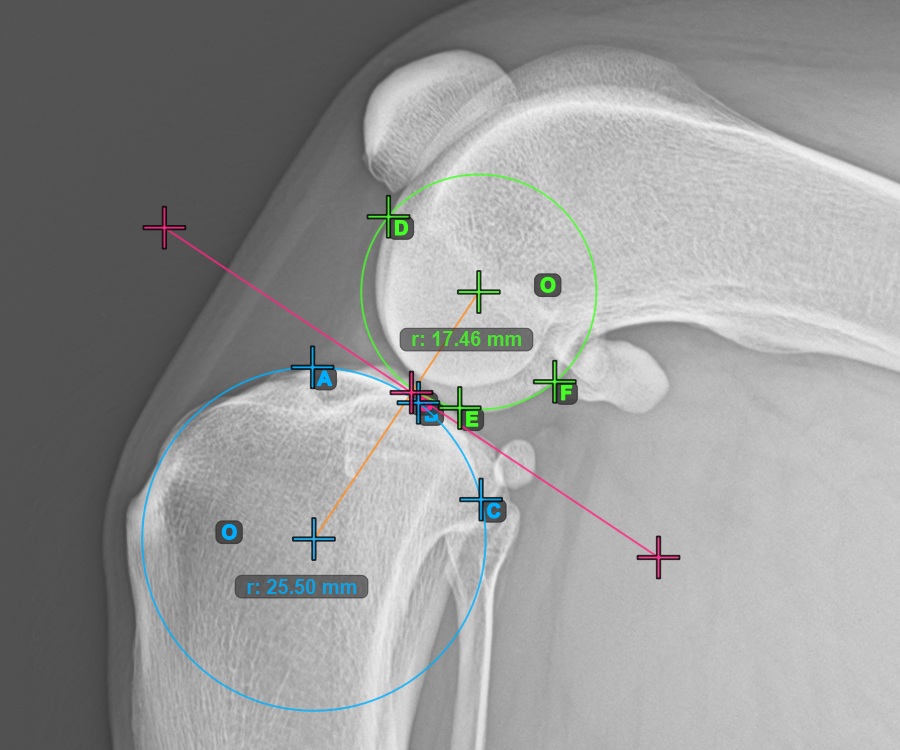

Starten Sie die Messung, indem Sie die drei Punkte am Condylus Medialis Tibialis markieren.

Markieren Sie die drei Punkte am Hauptkondylus des Tibiaknochens (Medialis Tibialis). Unabhängig von der Reihenfolge stellen Sie sicher, dass Sie den vordersten Punkt, den hintersten Punkt und den Mittelpunkt des Medialis Tibialis markieren. Basierend auf den drei gesetzten Punkten wird automatisch ein Kreis konstruiert.

Das Bild unten zeigt die typische Platzierung der drei Punkte am Condylus Medialis Tibialis.